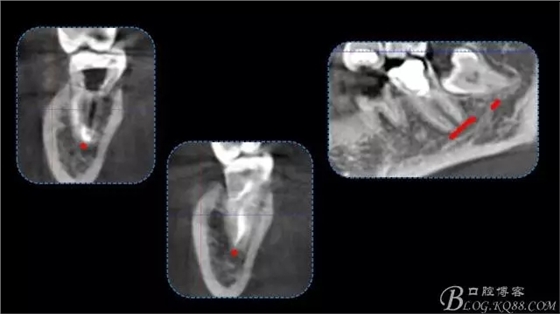

640.webp (4).jpg

640.webp (5).jpg